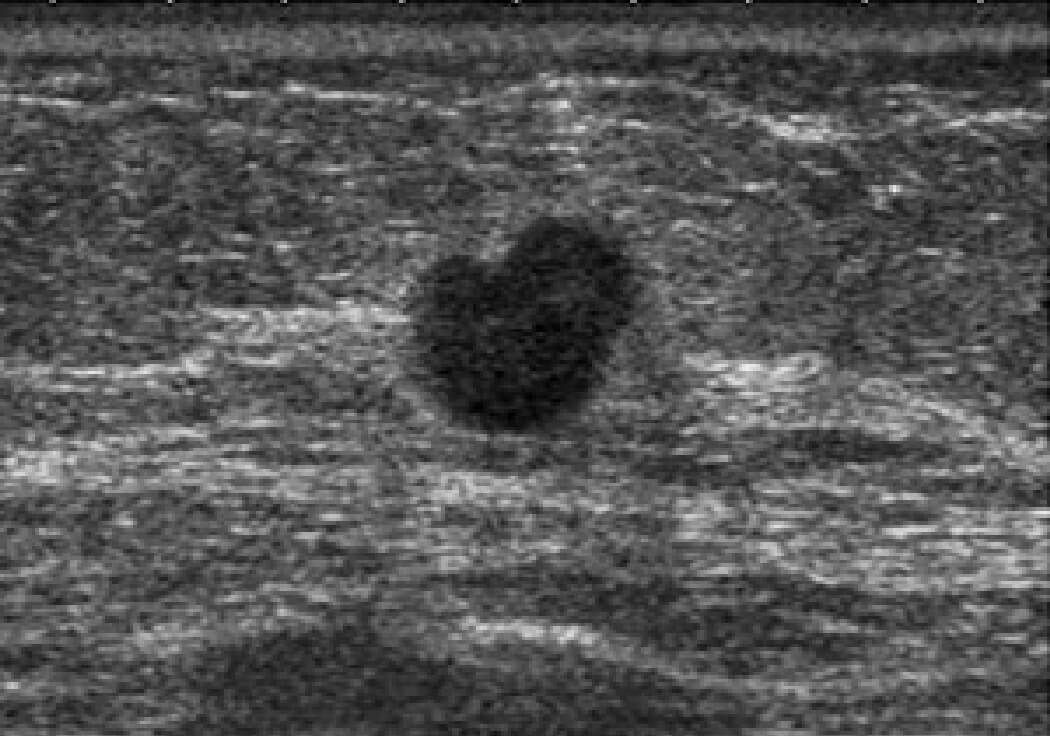

乳房超音波検査

乳がんの症例2